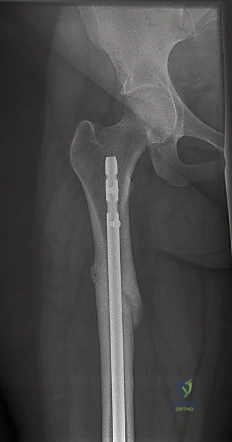

صورة شعاعية توضح كسراً حاداً في عظم الفخذ ناتجاً عن صدمة عالية الطاقة، مما يستدعي تدخلاً جراحياً فورياً.

* الأشعة السينية (X-rays): هي الفحص الأساسي والضروري. يتم أخذ صور من زوايا متعددة (أمامية وجانبية) للفخذ بالكامل، بالإضافة إلى تصوير مفصلي الورك والركبة لاستبعاد أي كسور مصاحبة غير ظاهرة.

* التصوير المقطعي المحوسب (CT Scan): يطلبه الدكتور هطيف في الحالات المعقدة، خاصة إذا كان الكسر يمتد إلى داخل مفصل الركبة، أو إذا كان الكسر مفتتاً جداً، وذلك لتخطيط العملية الجراحية بدقة ثلاثية الأبعاد.

التشخيص الدقيق بالأشعة السينية يحدد نوع الكسر وموقعه، وهو الخطوة الأولى في وضع خطة العلاج الجراحي.